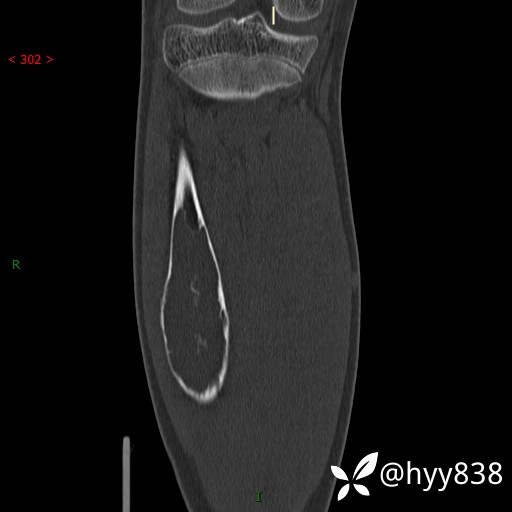

CT MPR COR

儿童,发现右小腿肿硬性肿物3年。资料齐全,ABC VS SBC VS FD--结果公布

临床诊断:胫骨肿物